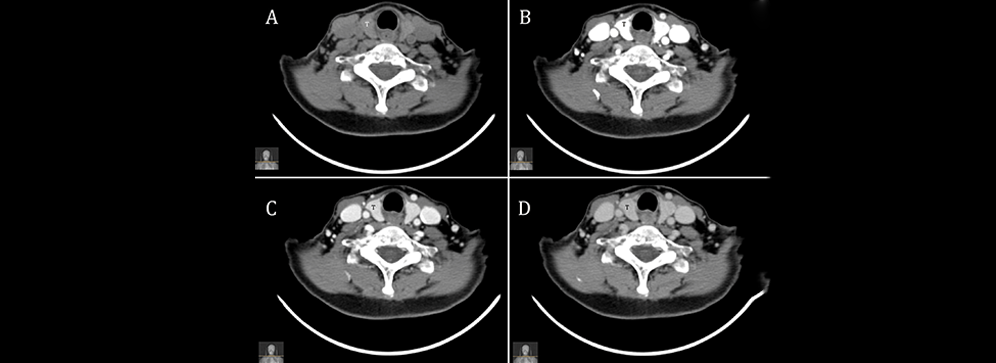

When it comes to detecting and treating parathyroid disorders, accurate imaging is the foundation of effective healthcare. At Insight Diagnostics and Labs, we proudly offer the advanced 4D CT Scan for Parathyroid in Pallavaram, a diagnostic innovation that helps doctors identify parathyroid abnormalities with unmatched clarity. Unlike traditional scans, this advanced imaging not only provides three‑dimensional views but also adds a dynamic element — the fourth dimension — showing how the glands change and function over time. This extra detail gives doctors a clear roadmap for diagnosis and treatment.

A 4D CT Scan for the parathyroid is a cutting‑edge imaging test that not only provides three‑dimensional pictures but also captures changes over time — the “fourth dimension.” This allows doctors to assess the location, size, and functionality of the parathyroid glands with remarkable detail.

Doctors often turn to a 4D CT Scan in Pallavaram when traditional imaging such as ultrasound or standard CT does not give sufficient clarity. Patients with suspected hyperparathyroidism, persistent high calcium levels, or a history of kidney stones are common candidates for this test. Unlike conventional scans, the 4D CT provides both anatomical and functional details, which are crucial for accurate diagnosis.

One of the biggest challenges in diagnosing parathyroid disorders is that the glands are small and can sometimes hide in unexpected places. Traditional imaging techniques often miss them, leading to delayed treatment and patient frustration. With a 4D CT Scan in Pallavaram, patients benefit from high‑resolution images that reveal both the structure and blood flow of the glands, giving doctors a comprehensive view.